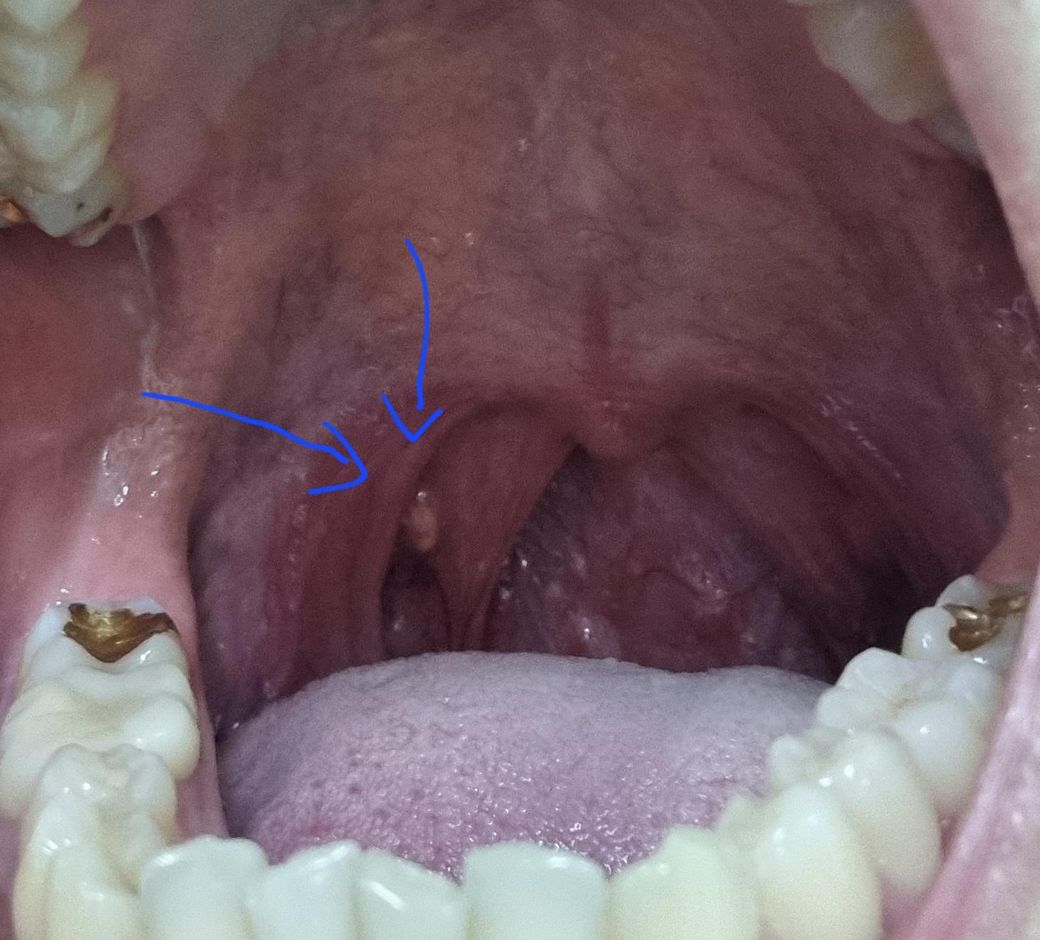

목구멍 안이 하얗게 돋아난 무엇인가를 어떻게 봐야할까요?

추가로 목 안에 하얀게 아직 염증이 있는걸까요

• 2번 째 사진

사진으로는 오른쪽 편도 결석이 의심되는 상태로 결석이 있는 경우,

빠져나오지 않는 경우, 주변으로 염증과 통증을 반복적으로 유발할 수

있습니다. 항생제 처방과 함께 따뜻한 음료를 마시고 호전이 없는 경우,

이비인후과 진료를 통해 시술을 통해 제거하는 것이 좋을 것으로

보입니다.

일단 병변이 작아서 정확한 진단을 하기는 어려우나 가능성이 있는 것으로는 편도에 음식물의 찌꺼기나 세균등이 침착하면서 생긴 편도결석일 가능성이 있어 보입니다. 만약 구취나 이물감이 있는 경우라면 편도 결석을 생각해 봐야 할 수 있어서 이비인후과에 방문하셔서 의사의 진찰을 받으시기 바랍니다.